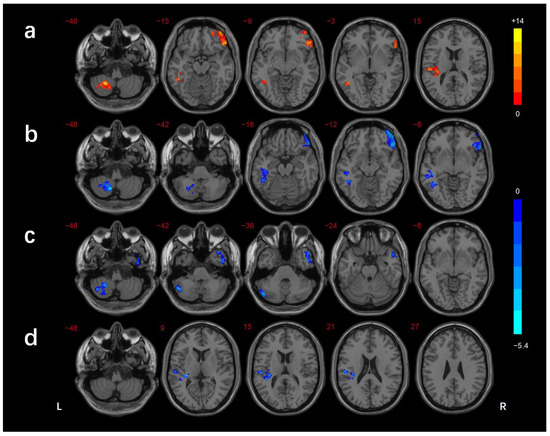

| Brain Regions | BA | Voxels (mm3) | Peak MNI Coordinates | f/t-Value | ||

|---|---|---|---|---|---|---|

| X | Y | Z | ||||

| ANOVA | ||||||

| R_MTG/ITG | 21/38 | 194 | 51 | 9 | −39 | 10.514 |

| R_MTG/ITG/FG/cerebellar lobule VI | 37/20 | 187 | 54 | −48 | −18 | 11.278 |

| L_ITG | 21 | 155 | −60 | −21 | −15 | 10.434 |

| R_IFG | 47 | 206 | 51 | 33 | −15 | 12.651 |

| DMCN vs. HC | ||||||

| L_MTG/ITG | 21 | 188 | −66 | −24 | −15 | −3.975 |

| B_MCC/R_precuneus | 24 | 188 | 15 | −24 | 42 | 3.665 |

| DMCI vs. HC | ||||||

| R_MTG/ITG | 21/38 | 185 | 51 | 12 | −45 | −4.018 |

| R_MTG/FG/cerebellar lobule VI | 37/20 | 299 | 39 | −24 | −18 | −3.908 |

| R_IFG | 47 | 229 | 48 | 30 | −12 | −4.243 |